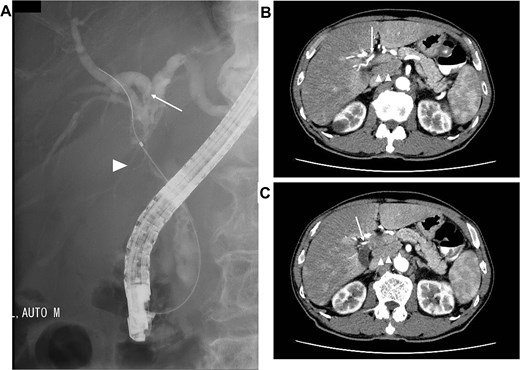

A 75-year-old male presented to our hospital owing to recurrent epigastralgia. Plain computed tomography (CT) revealed slight intrahepatic bile duct dilation and common hepatic duct (CHD) stenosis. Laboratory test results demonstrated elevated serum concentrations of alanine aminotransferase (49 U/ml), γ-glutamyl transpeptidase (287 U/ml), and CA19–9 (52.0 U/ml). Endoscopic retrograde cholangiography (ERC) revealed CHD stenosis and irregular wall at the confluence of the right anterior and posterior bile duct to the left hepatic duct (Fig. 1A). Biopsy of the stenosed CHD revealed adenocarcinoma. Dynamic CT revealed a 2-cm-diameter mass consistent with CHD stenosis, suggesting right hepatic artery (RHA) invasion (Fig. 1B). Furthermore, a swollen lymph node around the common hepatic artery and the retropancreatic area was noted (Fig. 1C). From these findings, the patient was diagnosed with borderline resectable perihilar cholangiocarcinoma with lymph node metastasis and vascular invasion (Bismuth Type IIIa, UICC cT3N1M0 Stage IIIC).

Images before neoadjuvant GCD immunochemotherapy (A) ERC revealing biliary stricture extending from the CHD (arrow head) to the hepatic hilum. Right posterior branch (arrow) joins the left hepatic duct. (B and C) dynamic CT demonstrating the tumor invades the RHA (arrow), and the lymph node surrounding the common hepatic artery and retropancreatic area is swollen (arrow head).